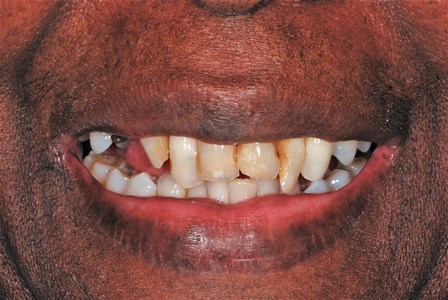

Before